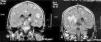

Paciente varón de 40 años, con antecedentes de tabaquismo y prácticas sexuales de riesgo, que consulta por un cuadro progresivo de unas 2 semanas de evolución de pérdida de fuerza en hemicuerpo izquierdo, alteraciones visuales y cefalea. No se refería fiebre ni cuadro constitucional. Exploración física general sin hallazgos, manteniendo el paciente buen nivel de conciencia y aceptable estado general. En la exploración neurológica se podía constatar una hemianopsia homónima izquierda, paresia facial central izquierda, hemiparesia izquierda (3/5) de predominio crural, con hemidisestesia y reflejos osteotendinosos exaltados ipsilaterales. Los análisis de laboratorio mostraron linfopenia (600/(l), con cifras de hemoglobina y plaquetas normales, estudios de coagulación y bioquímicos dentro de la normalidad, incluyendo función renal, perfil hepático, LDH y sistemático de orina. La radiografía de tórax y el ecocardiograma transtorácico fueron normales. Se realizó una TC craneal que evidenciaba múltiples lesiones focales supratentoriales, hiperdensas en el estudio sin contraste en relación con hemorragia de las mismas, con realce tras contraste intravenoso y edema vasogénico periférico (fig. 1). La RM craneal mostraba múltiples lesiones focales supra e infratentoriales, hiperintensas en las secuencias potenciadas en T1 y en T2, muchas de ellas con realce heterogéneo tras la administración de contraste y con hemorragia (fig. 2). Se completaron estudios microbiológicos que confirmaron infección por VIH con serología positiva (ELISA y W. Blot), carga viral de 4,36 log10 copias/ml, CD4: 11,9% (71/mm3), serología toxoplasma IgG positiva, despistaje negativo de otras coinfecciones y patologías oportunistas (serología LUES, VHB y VHC negativas, baciloscopias y cultivo micobacterias de esputo y orina negativos, test de Mantoux negativo, determinación de antígeno criptocócico en suero negativo y PCR de citomegalovirus en plasma negativa).